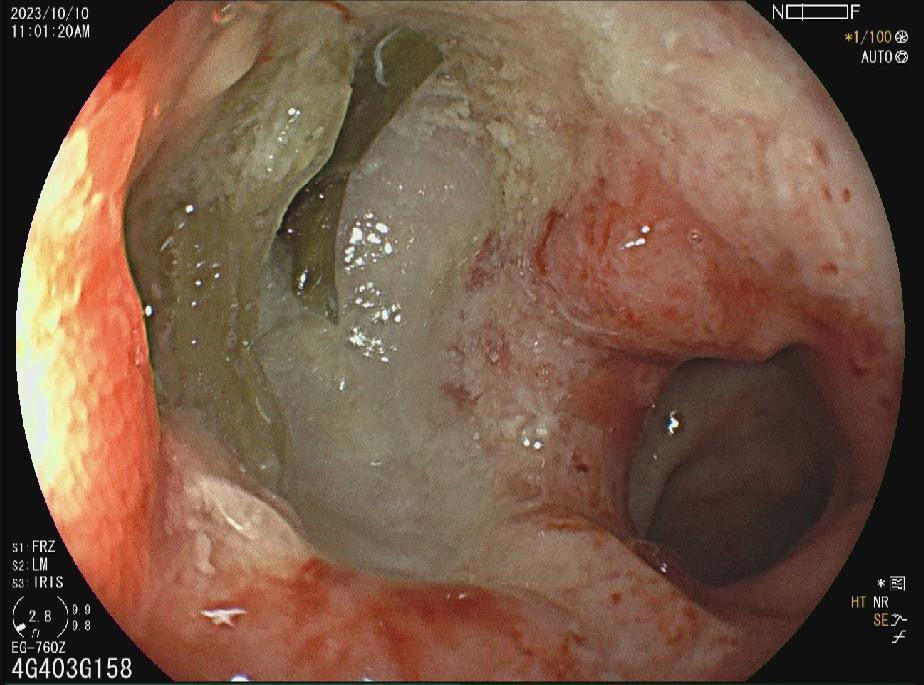

十二指肠球部溃疡

胃窦多发溃疡

胃窦溃疡

胃角溃疡

HPA感染鸡皮样胃炎

胃癌